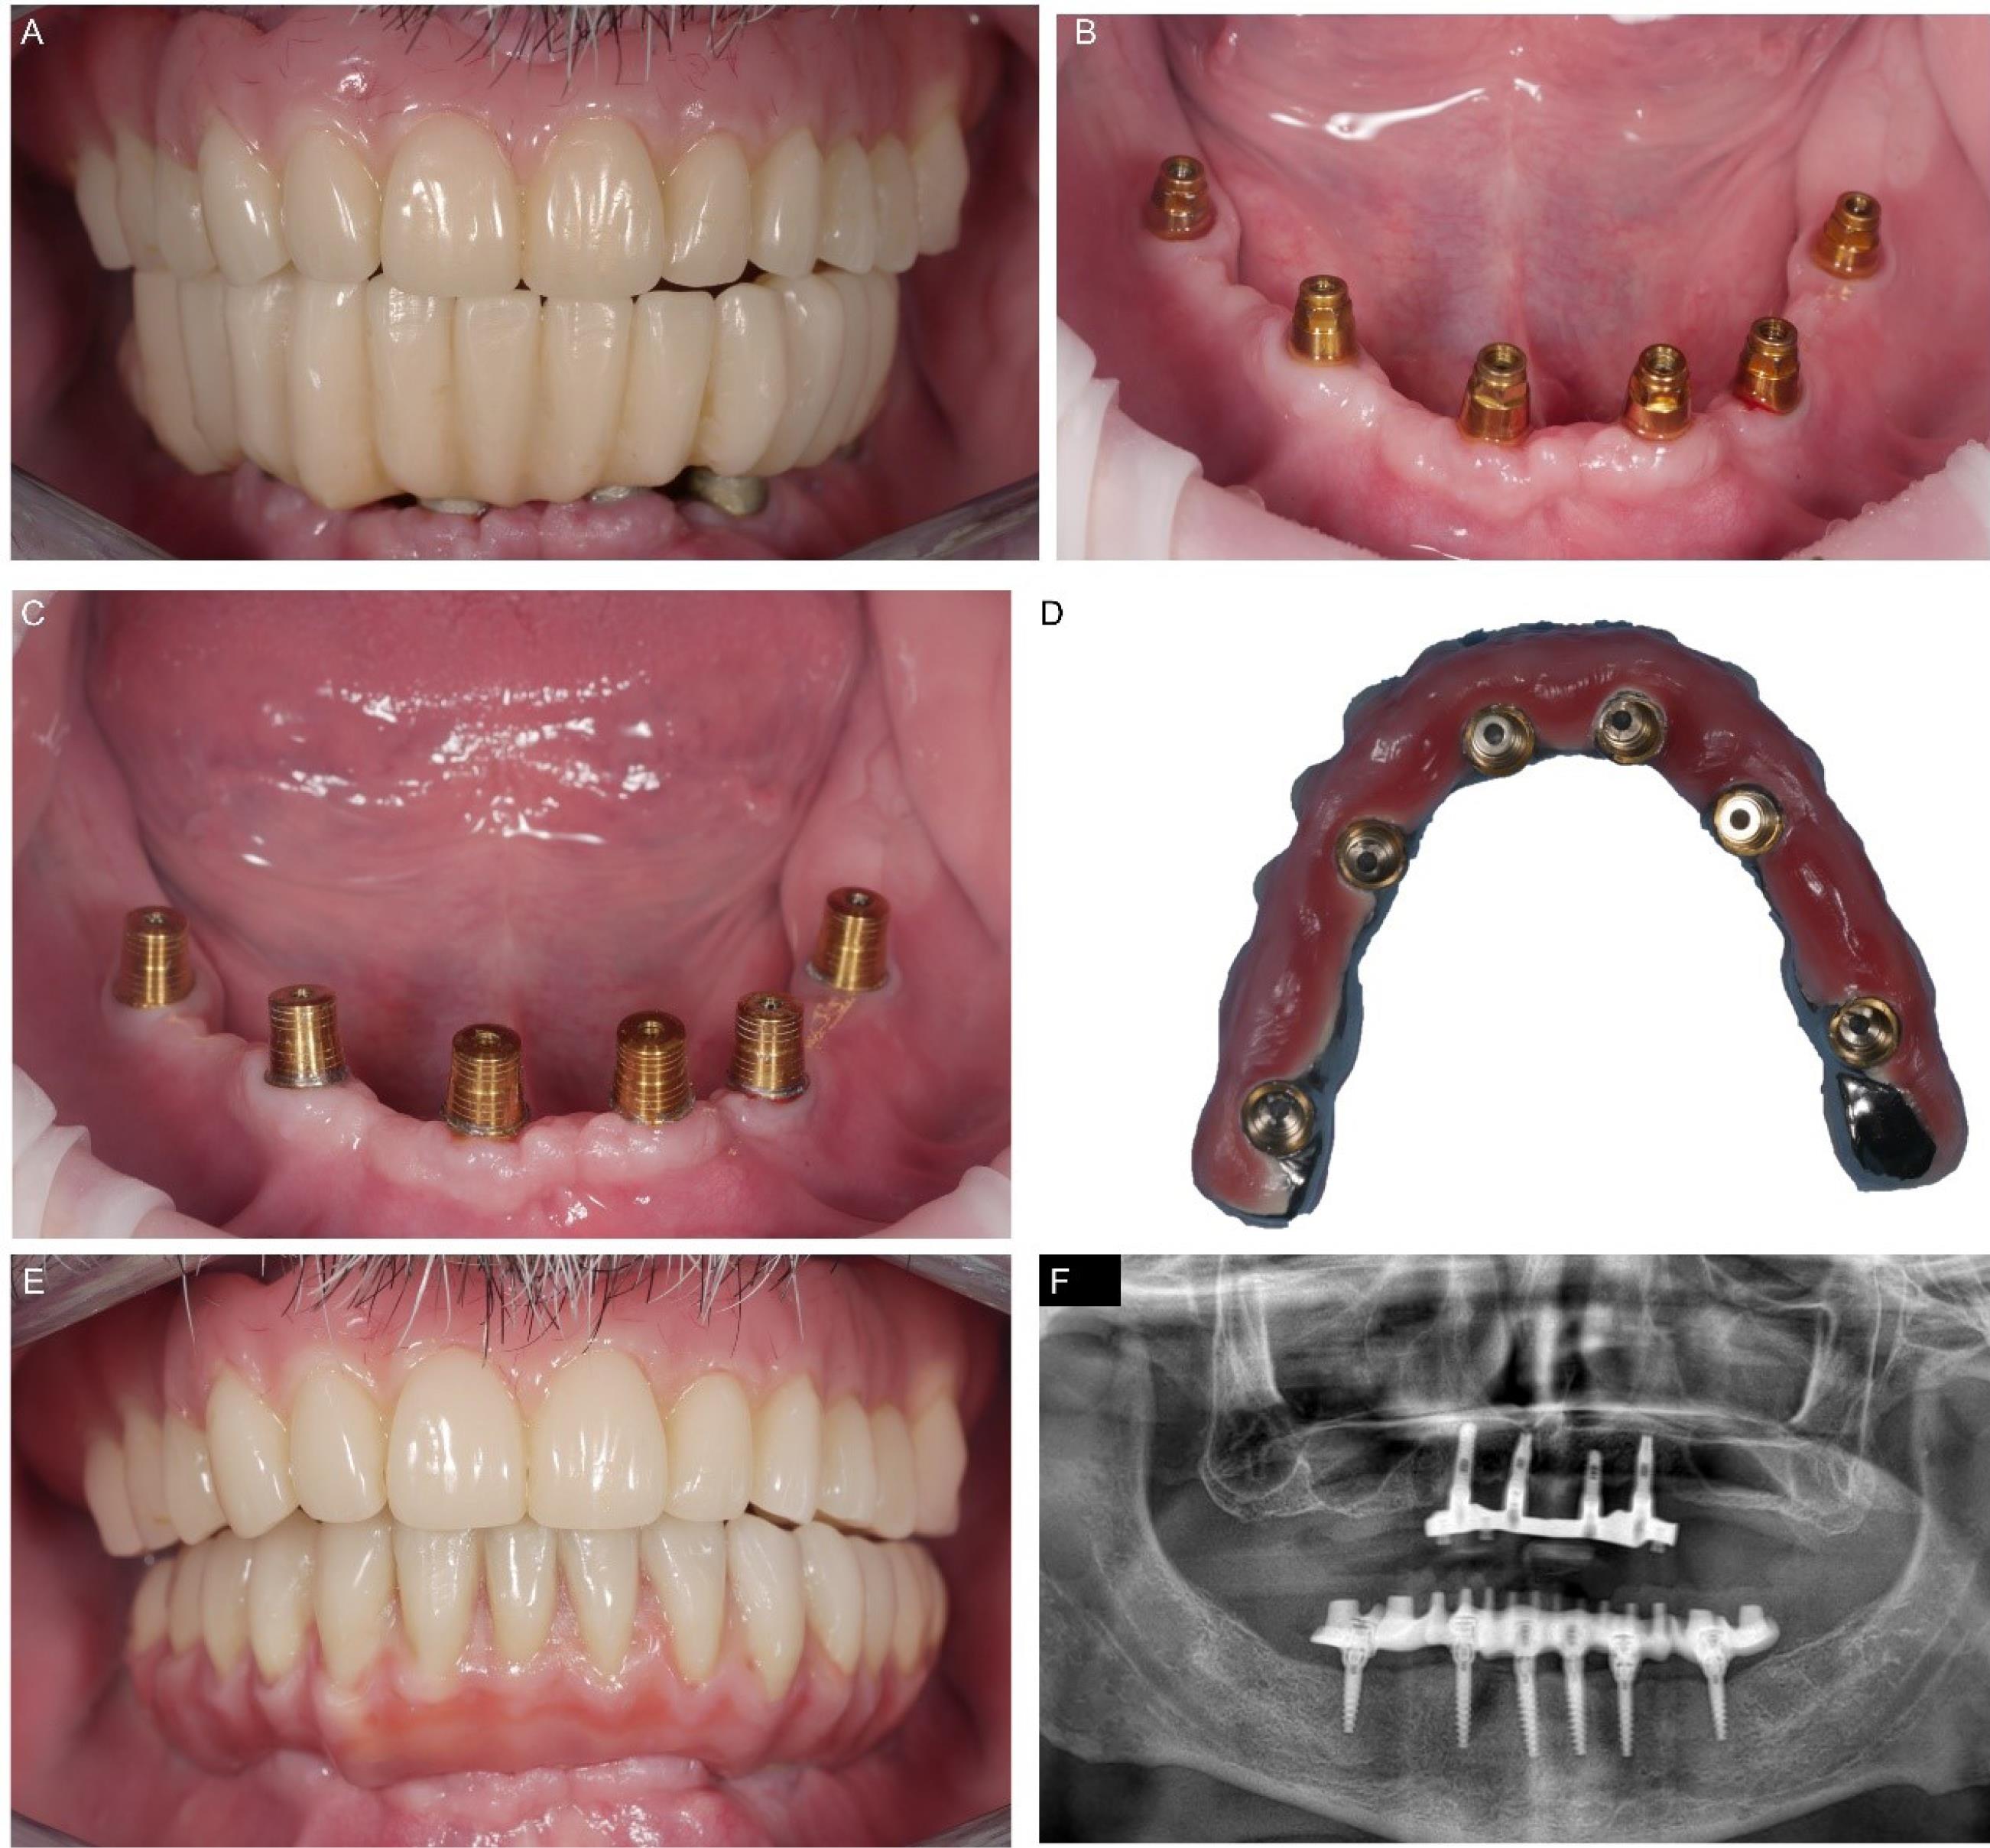

The patient reported minimal hematoma and ecchymosis in the submandibular region, which resolved within ten postoperative days. The control checks were carried out weekly in the first month after the immediate loading and every 15 days until the definitive prosthesis connection session. No complications or problems were recorded. After three months, the definitive structure was connected with a conical joint system. In the meantime, a new removable denture for the upper jaw was projected and connected to the metallic framework to correct the occlusal relationship with the new mandibular rehabilitation. No complications or radiological peri-implant bone resorption occurred at a weekly follow-up rate in the first month and monthly in the first two years after surgery (Figure 5).

Figure 5.

Final prosthesis delivery. Clinical situation three months after treatment with (A) and without (B) the temporary superstructure. Cap positioning and activation (C), and cementation of these inside the definitive prosthesis (D). Final placement of the definitive device (E), and panoramic x-ray after one year(F)